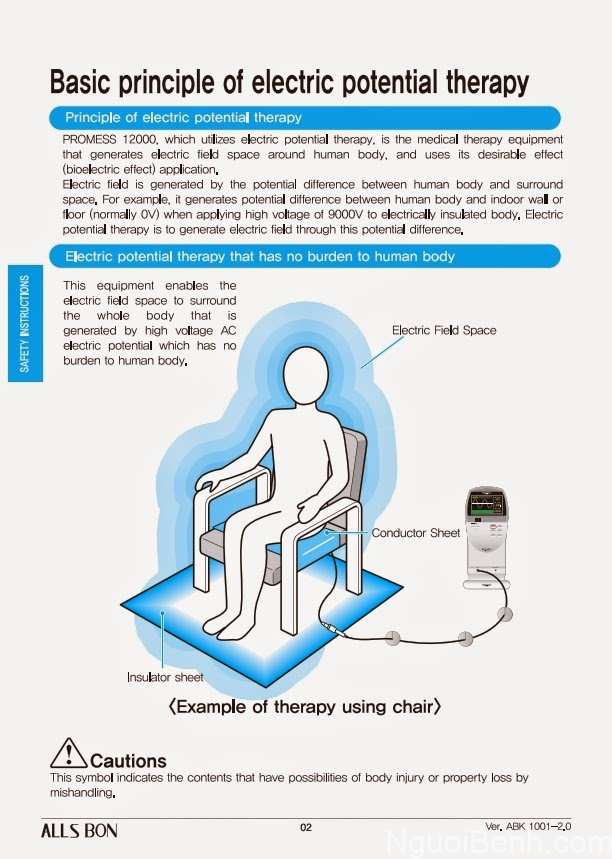

Bằng cách sử dụng dòng điện xoay chiều có điện áp cao và sóng tần số thấp, người ta có thể tạo ra một điện trường cao áp ứng dụng trong vật lý trị liệu chuyên sâu.

Mô phỏng nguyên lý hoạt động của điện trường cao áp

Trong ví dụ về mô phỏng nguyên lý hoạt động của máy điện trường cao áp ở hình bên trên, người dùng đang ngồi lên một tấm thảm dẫn điện nối trực tiếp với máy. Khi bật chế độ trị liệu, máy sẽ truyền một dòng điện có mức điện áp cao vào thảm dẫn điện (mức điện áp có thể là 9000V – 12000V – 14000V…).

Thảm dẫn điện lúc này trở thành cầu nối giữa máy và người sử dụng. Dòng điện sinh học bên trong cơ thể người kết hợp cùng điện áp cao từ máy khiến người dùng trở thành 1 vật tích điện/ vật mang điện/ vật nhiễm điện, tức là người dùng đang có hiệu điện thế lớn hơn 0.

Tuy nhiên, chân người dùng lại đang đặt lên 1 tấm thảm cách điện có hiệu điện thế = 0V. Điều này tạo nên sự chênh lệch điện áp giữa cơ thể người với mặt đất, và không có dòng điện nào được sinh ra giữa cả hai, từ đó khiến cho điện trường cao áp được hình thành.

Điện trường là một môi trường có chứa điện tích. Vậy nên các điện tích có trong điện trường cao áp vừa được tạo ra sẽ tương tác với điện tích màng tế bào trong cơ thể người, từ đó kích thích tế bào trao đổi chất, điều chỉnh cân bằng axit-bazơ & chất điện giải trong máu, cải thiện chức năng thần kinh tự chủ, tăng cường khả năng miễn dịch… nhằm phòng ngừa và điều trị các loại bệnh lý. [15]